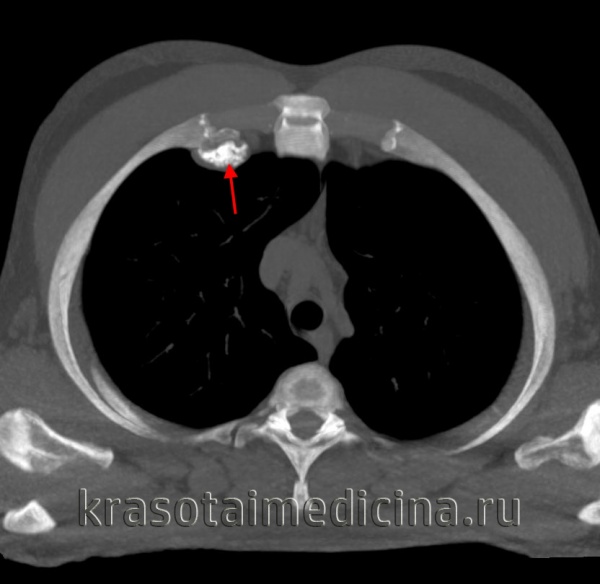

- Новообразования ребер чаще всего развиваются из реберно-хрящевых соединений; могут принимать вид легочных узлов